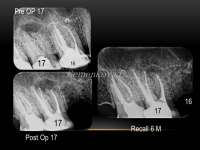

14734399434650.jpg (61Кб, 960x720)

14734399434661.jpg (64Кб, 960x720)

>>514662

Грамотный терапевт с микроскопом тебе нужен. На крайняк - апикальная хирургия.

пики из паблика, который чекаю. Кейс одного из докторов. Мб что-то поймешь. Сравни со своей НЕХ и вот что с ней можно сделать

Ты кажется стрелку не на тот зуб показал на своём пике. У тебя там зуб без пломбы даже. кек.

Мосты - хуйня. Избегай их. Только имплант если уж решишь удалять

>>514665

Нет. Ценник лечения увеличивается.